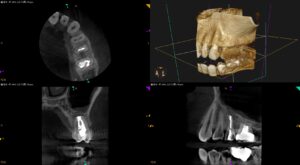

96%の成功に入らなかった歯牙の外科治療〜#13 Intentional Replantation 2M recall

以前の治療の経過観察。 96%の成功に入らなかった歯牙の外科治療〜#13 Intentional Replantation Intentional Replantationから2ヶ月が経過した。 歯牙はどうなっただろうか … 続きを読む 96%の成功に入らなかった歯牙の外科治療〜#13 Intentional Replantation 2M recall